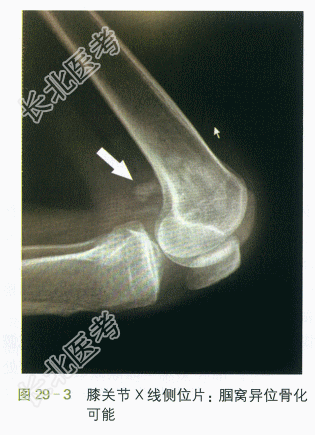

(2)影像学检查:①术前头颅CT示脑挫裂伤,右颞硬膜下血肿,左颞硬膜外血肿,左侧颞骨骨折,颅内积气,蛛网膜下腔出血,鼻窦炎,如图29-1所示。②术后头颅CT示右颞硬膜外血肿去骨瓣术后表现,脑挫裂伤,左筛窦及双蝶窦炎症,左侧颞骨骨折,如图29-2所示。③左膝关节片示左膝关节腘窝处异位骨化可能,如图29-3所示。④髋关节片示两侧髂前上棘及左侧股骨上段考虑异位骨化,左侧股骨头密度改变(考虑骨质疏松可能),如图29-4所示。